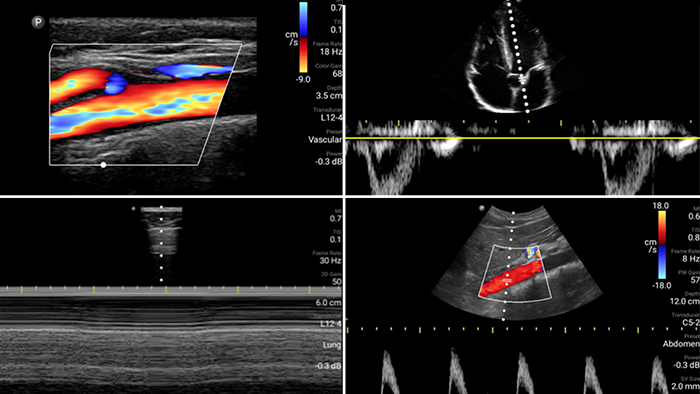

Evalúe, diagnostique y trate a sus pacientes en minutos con un examen POCUS de puntos múltiples.

Lumify puede ayudar a evaluar a los pacientes más rápido y a mejorar la precisión en el diagnóstico de las causas comunes de disnea y otras afecciones pulmonares.

Los pacientes que sufren un ataque cardíaco necesitan atención inmediata. Los ajustes cardíacos preestablecidos de Lumify pueden ayudar a los pacientes a ser diagnosticados más rápido para mejorar sus resultados.

• Rango extendido de frecuencias de operación de 4 a 1 MHz • 2D, Doppler a color, Modalidad M, XRES avanzado e imágenes armónicas multivariables • Imágenes de alta resolución para aplicaciones abdominales y cardíacas: las optimizaciones de preajustes de imágenes cardíacas, gineco-obstétricas, pulmonares, abdominales y FAST de Lumify ayudan a la tecnología que salva vidas en entornos prehospitalarios